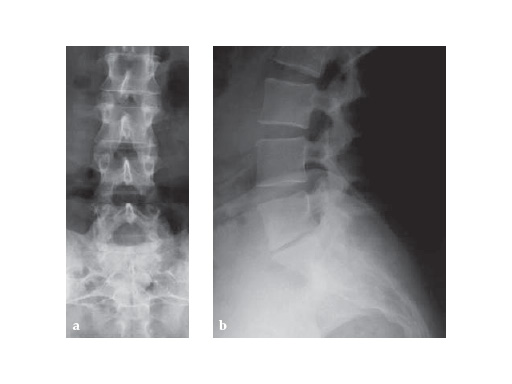

Case 1

44-years-old Firefighter2 years of increased low back pain